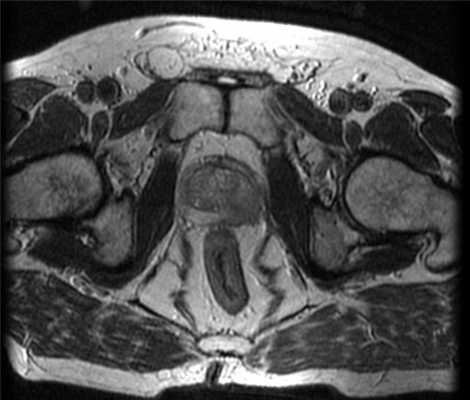

Рис. 1. МРТ (Т2-взвешенные изображения) картина поражения левой доли предстательной железы.

(Слева) Т2-ВИ, аксиальный срез через верхушку предстательной железы: гипоинтенсивный очаг в периферической зоне левой доли. Визуализируется зона широкого контакта очага с капсулой и ее выпячивание.

(Правый) На поперечном трансректальном УЗ срезе в левой ПЗ визуализируется локализованное гипоэхогенное образование (частично выделено желтой пунктирной линией). Разметка соответствует ходу иглы при биопсии. При гистологическом исследовании после биопсии под МР-УЗИ контролем верифицирована аденокарцинома 4+4 по Глисону (Левый) На аксиальном Т3 МР срезе визуализируется увеличенная предстательная железа, в левой ПфЗ которой расположен очаг с нечеткими контурами и экстрапростратическим распространением, прорастающий в левый СНП. Обратите внимание на гиперплазированную переходную зону, сдавливающую ПфЗ, и сигнал неоднородной интенсивности от костного мозга со значительно гипоинтенсивной правой вертлужной впадиной, что соответствует распространенным костным метастазам (подтвержденным позднее при сцинтиграфии костей).